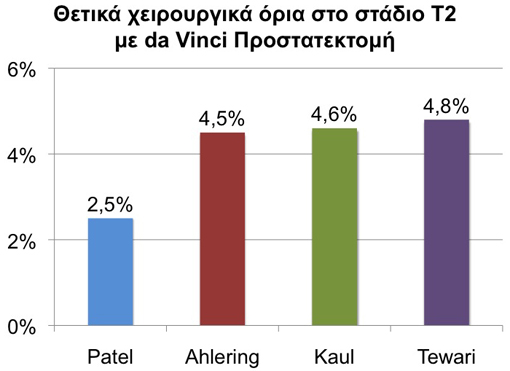

Σχετικά με τον έλεγχο του καρκίνου η da Vinci προστατεκτομή εμφανίζει παρόμοια ή και λιγότερα θετικά χειρουργικά όρια (εννοώντας όρια με καρκινικά κύτταρα που πιθανόν να έμειναν πίσω) σε σύγκριση μ’ άλλες μορφές χειρουργικής θεραπείας όπως αποδεικνύεται σε μεγάλες συγκριτικές μελέτες.

Σε διάφορες μεγάλες δημοσιευμένες μελέτες η da Vinci Προστατεκτομή έδειξε ίδια και λιγότερα ποσοστά θετικών χειρουργικών ορίων (την εκτίμηση δηλαδή εάν έμειναν πίσω καρκινικά κύτταρα) συγκρινόμενη με άλλες μορφές χειρουργείου.

Τα θετικά χειρουργικά όρια μετά από da Vinci ριζική προστατεκτομή είναι σημαντικά λιγότερα σε σχέση μ’ άλλες χειρουργικές θεραπείες. Τα ονόματα παραπέμπουν στους συγγραφείς των μελετών.

Η κατάσταση των χειρουργικών ορίων αναφέρεται στην παρουσία ή όχι καρκίνου σε επαφή με την εξωτερική επιφάνεια του προστάτη που αφαιρέθηκε. Αρνητικά χειρουργικά όρια σημαίνει ότι ολόκληρη η εξωτερική επιφάνεια του προστάτη είναι ελεύθερη από καρκιικά κύτταρα και ότι ό καρκίνος περιβάλλεται από υγιή στρώματα ιστών και άρα έχει αφαιρεθεί πλήρως. Τα αρνητικά χειρουργικά όρια είναι ένας πολύ καλός δείκτης ότι όλος ο καρκίνος έχει πλήρως εξαιρεθεί.

Ο έλεγχος του καρκίνου του προστάτη διαφέρει και εξαρτάται κυρίως από το προεγχειρητικό στάδιο του καρκίνου και από την εμπειρία του χειρουργού. Για πρώτη φορά με την ρομποτική τεχνολογία δίνεται η ευκαιρία να μειωθεί η συμβολή του ανθρώπινου παράγοντα (του χειρουργού δηλαδή) στην παραμονή των θετικών χειρουργικών ορίων και συνεπώς στον καλύτερο έλεγχο του καρκίνου του προστάτη.